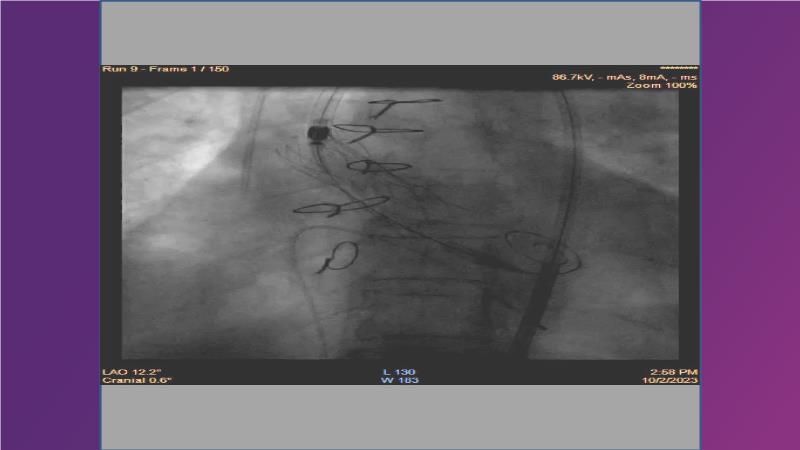

Gain expertise in selecting the appropriate TAVI device for achieving stable deployment in a 90-degree horizontal aorta. Discover techniques for ensuring smooth deliverability, particularly when navigating through tight and tortuous anatomies. Additionally, learn strategies to prepare for future coronary access, irrespective of the height of the left or right coronaries.

• To witness smooth deliverabilty even crossing tight and tortous anatomy

• To be ready for future coronary access regardless of the height of left or right coronaries